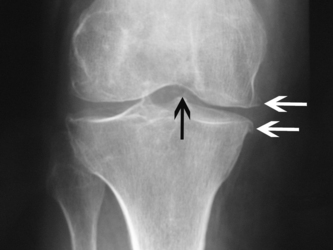

CPPD crystals can be identified by compensated polarised light microscopy of aspirated synovial fluid as rhomboid or rod-shaped crystals with weak positive birefringence. Plain radiographs may show chondrocalcinosis or the structural changes of OA. Chondrocalcinosis mainly affects fibrocartilage and is most commonly seen at the knee (Fig. 23.2), wrist and symphysis pubis. Screening for haemochromatosis, hyperparathyroidism, hypomagnesaemia and hypophosphatasia is indicated under the age of 55 years and when radiographic chondrocalcinosis is particularly striking and widespread (Wright & Doherty 1997).

image

Figure 23.2 X-ray of the knee showing tibiofemoral chondrocalcinosis (black arrow), medial compartment loss of joint space and medial osteophytes (white arrows) - pyrophosphate arthropathy.